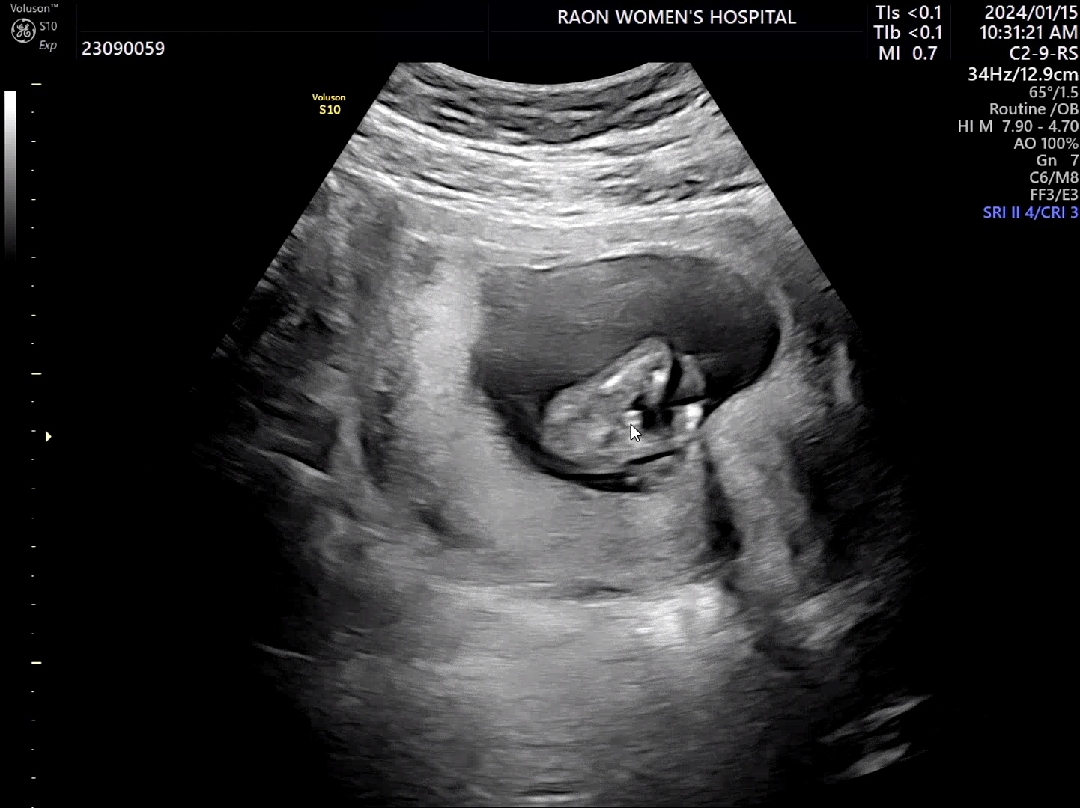

12주차 5일 각도법 필요 없는 성별 확인

기형아 검사하러 병원 갔는데 아기가 너무 적나라하게 보여줘서 성별 확정됐어요ㅋㅋㅋㅋㅋㅋ 원장님이 이건 꼬리일수가 없다고... 모두가 딸일 것 같다고 했는데 아들맘이 되었습니당🫶